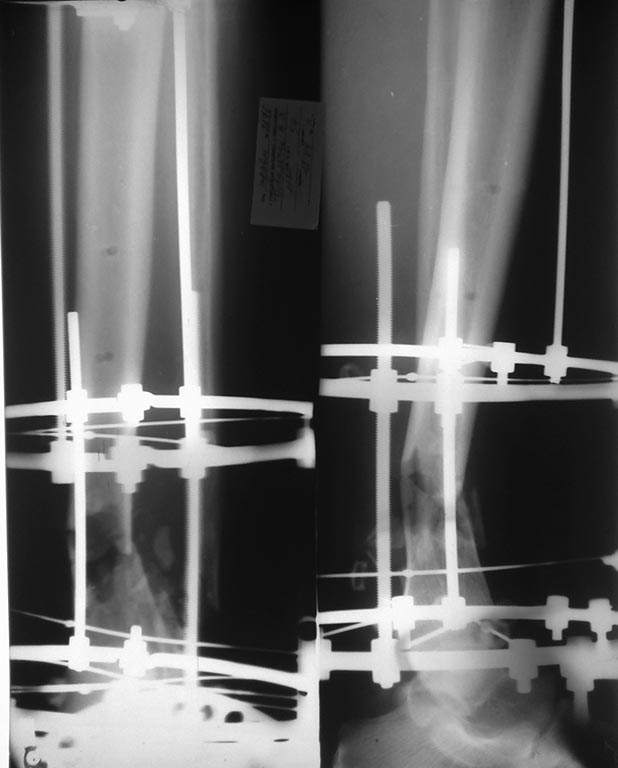

Уважаемые коллеги! Пациент мужчина 57 л, работающий, курящий,

периодически злоупотребляющий алкоголем. Травма 25.07.2013

дорожно-транспортная (ехал на велосипеде, был сбит легковым автомобилем)

- открытый (II-й ст по GA) оскольчатый перелом н/з обеих костей левой

голени.

ПО дежурству ПХО раны (рана по внутренней поверхности голени в н/з),

стабилизация отломков аппаратом внешней фиксации (стержневым). Через 4

дня у больного развился тяжелый алкогольный делирий, самостоятельно

демонтировал аппарат!, после чего ходил на этой ноге по отделению. Через

сутки после этого повторная операция - повторная обработка раны (которая

уже увеличилась в размерах), удаление свободных  костных фрагментов,

стабилизация отломков аппаратом Илизарова. Из делирия вышел,

компенсирован. Картина на данный момент на фотографиях  - Р-графия и

состояние раны. Кожные покровы по наружной поверхности также с участками

некрозов. Температуры нет, анализы спокойные, из раны серозное отделяемое.

Возникает вопрос - что дальше? Как вариант планируется резекция

пораженной большеберцовой кости (навскидку до 5 см), малоберцовой кости,

постепенная компрессия в аппарате до сближения отломков, заживление

раны. По сращению перелома, при адекватности пациента - решение вопроса

об удлинении конечности.